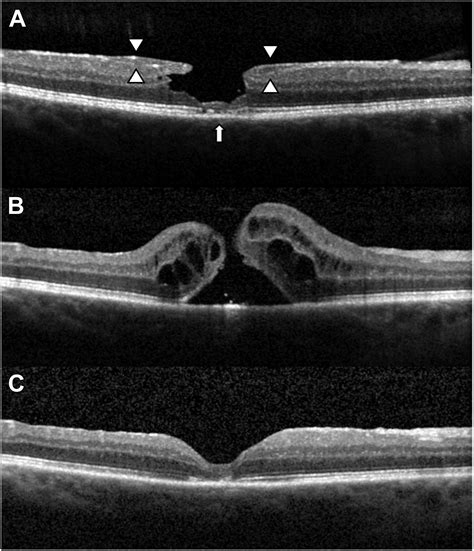

The standard treatment for this condition is a procedure known as a pars plana vitrectomy. During this surgery, an ophthalmologist specialized in retinal disorders removes the vitreous gel that is pulling on your macula. Once the gel is cleared, the surgeon places a gas bubble inside the eye to act as a temporary “splint.” This bubble presses against the edges of the macular hole, keeping them in place so the tissue can naturally seal and heal.

• Membrane Peeling: Surgeons often remove a thin layer of tissue called the internal limiting membrane (ILM) to relieve residual traction.

The prognosis for Macular Hole Surgery is generally very positive. For the vast majority of patients, a single surgery is enough to close the hole successfully. Once the hole is closed, vision usually improves significantly. While most people do not regain 2020 vision, the reduction in the central blind spot and the restoration of better reading vision allow patients to resume most of their normal daily activities. It is important to have realistic expectations and maintain regular follow-up visits with your retina specialist to monitor the progress of your recovery.